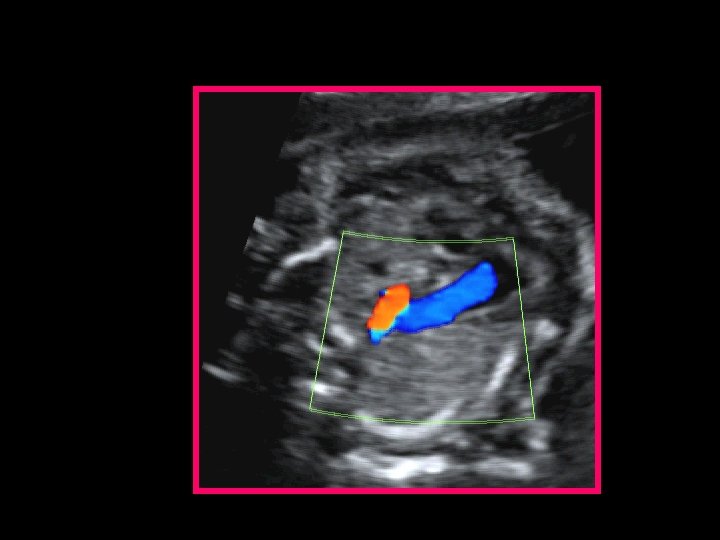

2) Color Doppler • Scansione 4 camere: efflusso sinistro flusso invertito forame ovale (sxdx) • Scansione 3 vasi: flusso invertito in aorta ascendente

Color Doppler: scansione “ 4 camere” • In diastole flusso preferenziale dall’atrio destro al ventricolo destro • Assenza di flusso nel ventricolo sinistro • Reverse - flow (sinistro-destro) attraverso il forame ovale LV LA RV LV RV RA LA RA

Color Doppler: scansione “ 3 vessel view” Flusso retrogrado in arco aortico ipoplasico

… Ricapitolando… (a) At 22 weeks’ gestation, on the 4 -chamber view, the severe hypoplasia of the left ventricle, transformed into a virtual cavity due to the mitral atresia (arrowhead) is evident (b) At 32 weeks’ gestation, there is severe hypoplasia of the left ventricle, which is slit-like (arrowhead). (c) In the same case as in (a), color Doppler demonstrates the mitral atresia (absence of left ventricular filling). (d) On the 3 -vessel view, the reverse flow across the hypoplastic aortic arch (in red, arrowhead) (associated tubular hypoplasia) confirms the aortic atresia.